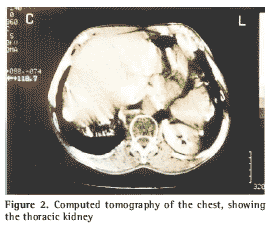

The patient reported rest as a factor for improvement and alcohol consumption as a factor for worsening of the profile. No trauma or any prior complaint of respiratory or urologic illnesses was reported. The patient was apparently well hydrated, presenting normal skin color and breathing normally. He presented no cyanosis, jaundice or fever. Upon physical exam of the chest, increased anterior-posterior diameter (barrel-shaped thorax) was found, as well as reduced chest expansion and hollow sounds in both lung bases, consistent with pulmonary emphysema. We requested chest X-rays in the posterior-anterior and lateral position. The X-rays showed a well-delimited, radiopaque oval-shaped mass at the base of the left hemithorax and in apparent contact with the diaphragmatic wall (Figure 1). Subsequently, we requested a computed tomography of the chest, where an oval-shaped area of extreme density was found at the base of the left hemithorax and was diagnosed as renal ectopia (Figure 2).

Prior to the advent of computed tomography, a diagnosis of thoracic kidney was confirmed, in most patients, through excretory urography(18). The use of computed tomography as a diagnostic procedure was previously reported by Grenadir & Larsen, chosen for its image quality and ease of interpretation(1).

In the differential diagnosis of thoracic mass, thoracic kidney should be considered. It is normally asymptomatic and may be identified, such as in the case in question, through computed tomography of the chest. This entity requires no specific treatment.